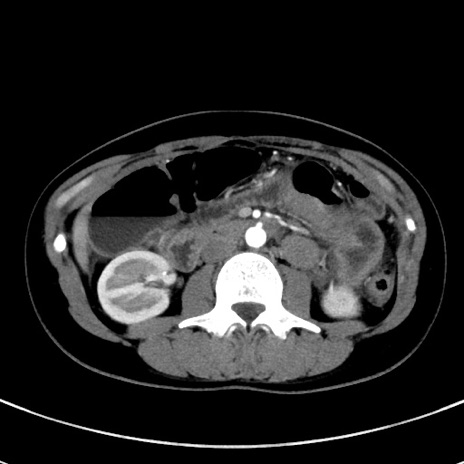

冠状断像

【症例】20歳代女性

【主訴】嘔吐、下腹部痛

【現病歴】昨日夕食後に嘔吐し下腹部痛が出現。本日になっても嘔吐持続し改善しないため来院。

【身体所見】意識清明、BT 37.2℃、BP 108/67mmHg、腹部:平坦、やや硬、下腹部正中から右にかけて圧痛あり、反跳痛軽度あり、tapping pain(+)。

【データ】WBC 13600、CRP 14.94